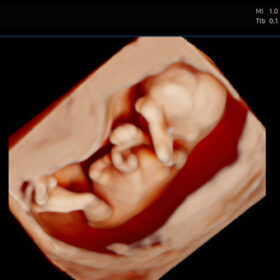

4D ultrasound builds on traditional 2D and 3D imaging by adding the element of real time motion. Instead of static three dimensional stills, 4D captures a live stream of your baby’s movements—allowing you to see yawns blinks and stretches as they happen. At its core lies advanced signal processing hardware and bespoke software algorithms developed by ultrasound innovators.

By rapidly sweeping the beam across a volume and capturing echoes from each direction, software reconstructs a three dimensional map of fetal anatomy. This volumetric dataset is then streamed continuously to create moving three dimensional renderings that can be rotated zoomed and sliced in real time.

Parents often marvel at seeing facial expressions and tiny movements. Yet not every session yields perfect clarity. Factors like fetal position low amniotic fluid or maternal tissue thickness can obscure details.

When explaining images use simple analogy like comparing echo intensity to light and shadow in photography. Highlight features gradually guiding parents through three dimensional orientation before switching back to real time mode.

3D ultrasound provides static three dimensional stills ideal for facial captures. HD imaging emphasizes contrast resolution and color rendering but remains a two dimensional plane. In contrast 4D adds the temporal dimension delivering fluid motion.